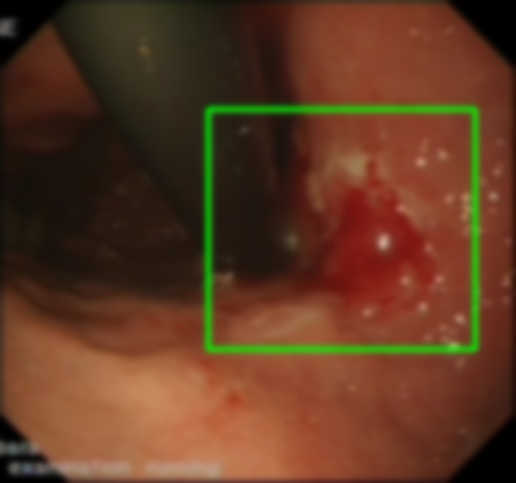

Gaussian Blur

Endoscopy GMAIMMbench Disease Diagnosis

Gaussian Blur - L0 (Original)

L0

L0 (Original)

Question

Focus on the square-highlighted area of this endoscopy image. What could be the potential diagnosis?

A barrett's esophagus B high-grade dysplasia C polyp D gastrointestinal tract cancer

Ground Truth: D. gastrointestinal tract cancer